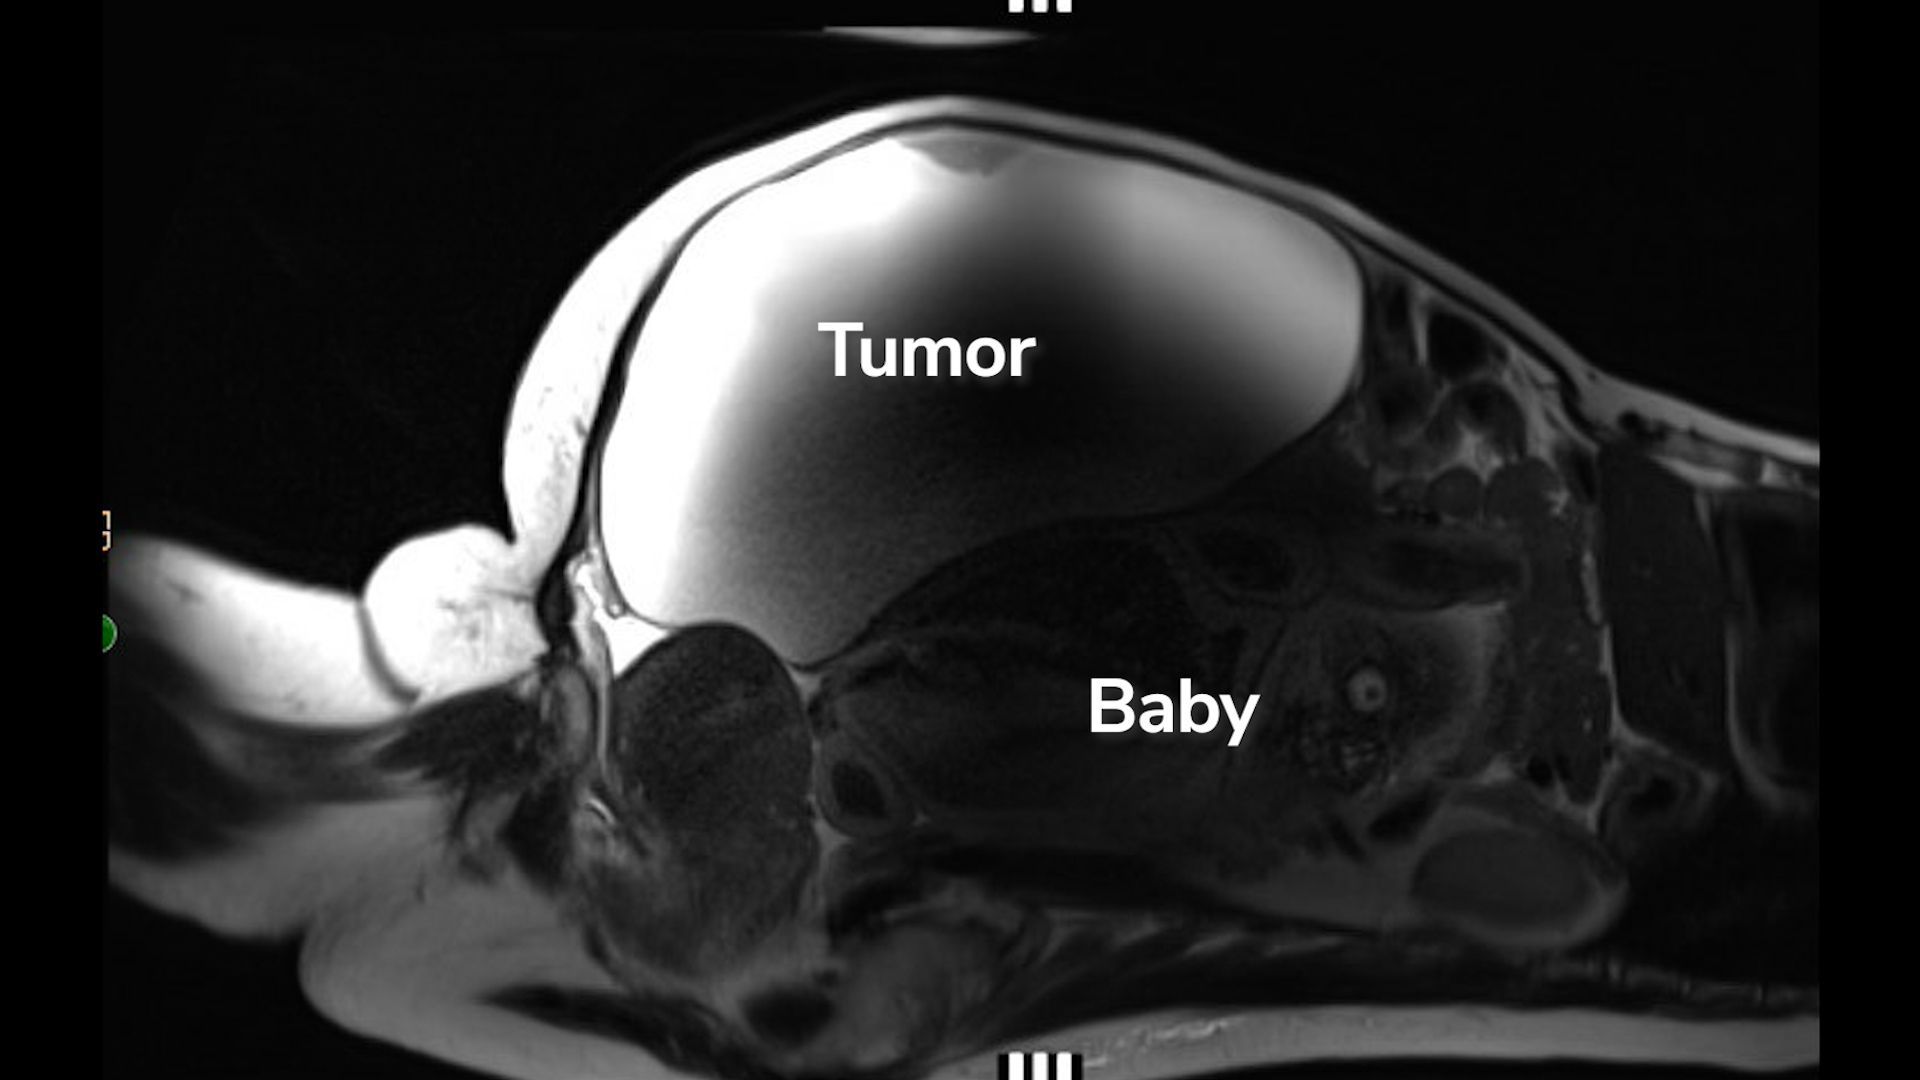

Lopez est arrivé à l’hôpital avec une tension artérielle très élevée et, pendant que le personnel médical commençait à le traiter, ils ont également effectué des analyses de sang et des examens corporels, notamment une IRM et une échographie. C’est alors qu’ils ont découvert que Lopez portait une rare grossesse extra-utérine. Le bébé était situé près du foie, son dos reposant à moitié sur l’utérus.

« C’était le bébé qui grandissait dans son ventre derrière la masse qui faisait tout sortir », Dr John Ozimekdirecteur médical du travail et de l’accouchement et de l’unité de soins materno-fœtaux à Cedars-Sinai, a déclaré dans la vidéo. « C’est pour ça qu’elle ne savait pas qu’elle était enceinte. »

Le bébé, nommé Ryu, a été découvert parce que Lopez devait avoir un poids de 9,9 kg. kyste de l’ovaire supprimé. Le kyste n’était pas cancéreux, mais il grossissait depuis des années au moment où Lopez devait subir l’opération.